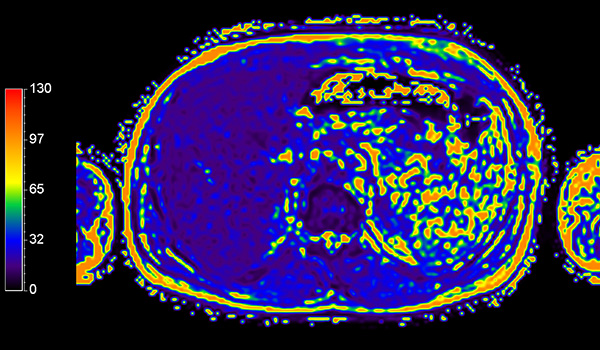

Axial mDIXON Quant (Fat Fraction)

Axial mDIXON Quant (T2*)